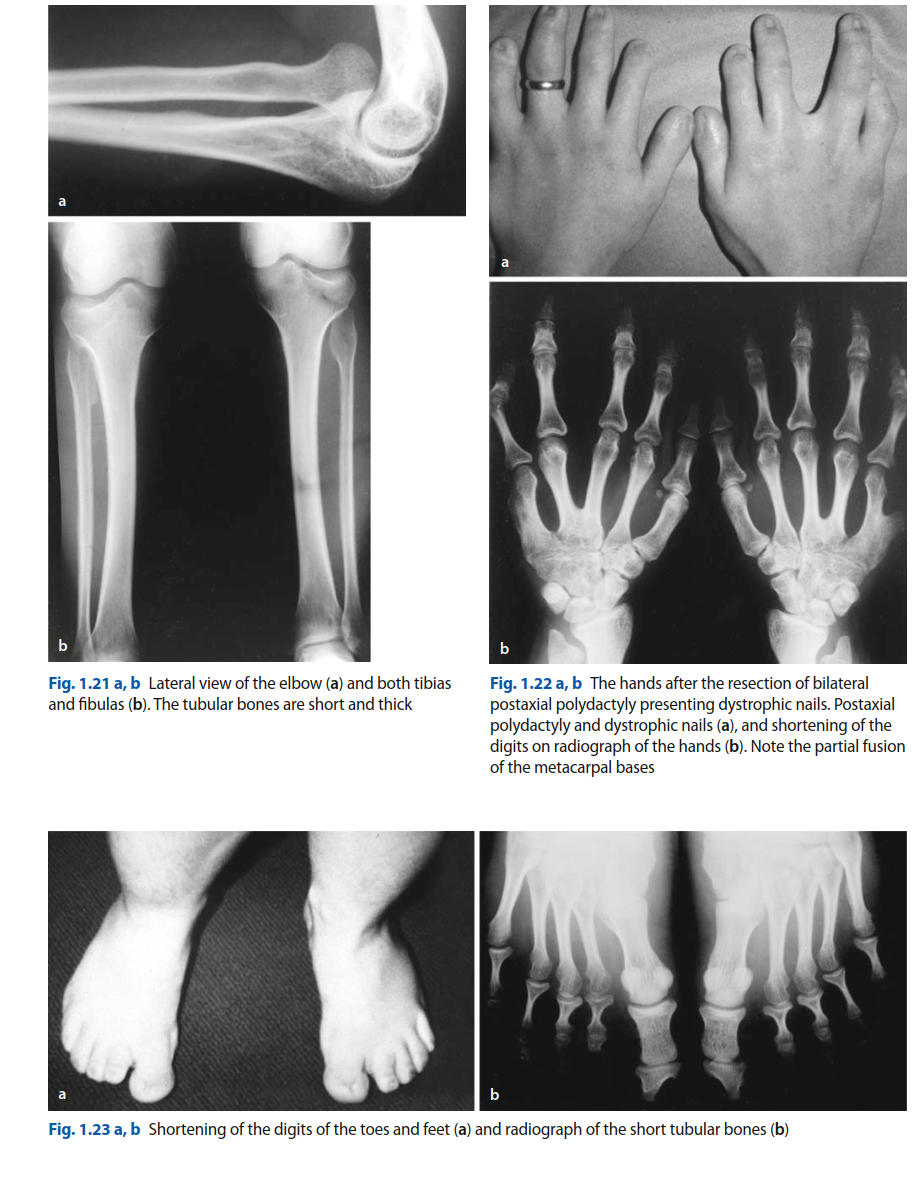

The clinical spectrum of EVC syndrome is broad, encompassing short-limbed dwarfism (mesomelic and acromelic types), postaxial polydactyly of both hands and feet, characteristic ectodermal dysplasias affecting nails and teeth, and a high incidence of congenital cardiac defects, most commonly an atrial septal defect (ASD). Oral manifestations include natal or neonatal teeth, supernumerary frenula, hypoplastic or dysplastic enamel, and abnormal dentition. Given its multisystemic nature, effective management necessitates a multidisciplinary approach involving orthopedics, oral and maxillofacial surgery, cardiology, pediatrics, and genetics. This review will delve specifically into the orthopedic and oral aspects amenable to surgical intervention, providing a comprehensive reference for clinical practice.

- Polydactyly: Postaxial polydactyly of the hands (often on the ulnar side) and feet is a hallmark feature, present in nearly all affected individuals. This can range from a rudimentary skin tag to a fully formed extra digit, often with its own metacarpal/phalangeal components and neurovascular supply. The presence and morphology of the extra digit significantly impact hand function, grip, and shoe wear.

- Carpal and Tarsal Anomalies: Carpal fusions, particularly of the capitate and hamate, are common, leading to reduced wrist mobility. Similar fusions can occur in the tarsal bones, affecting foot mechanics.